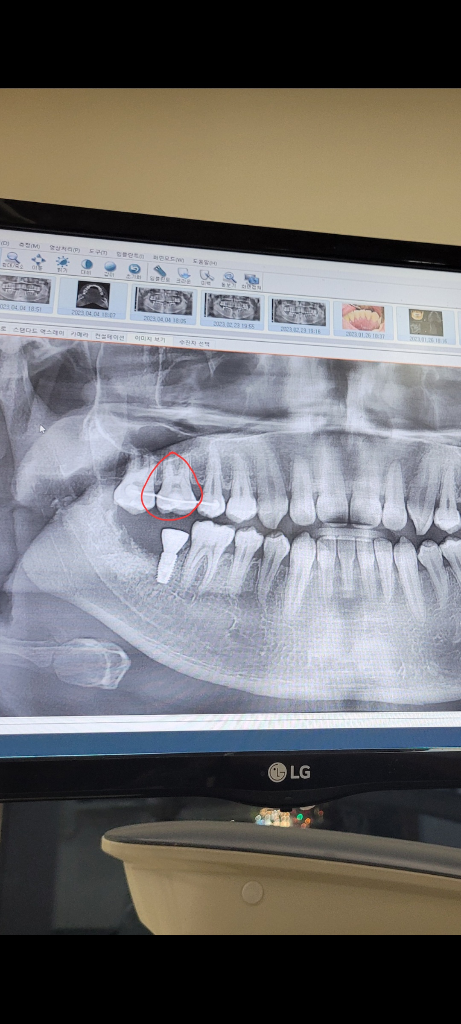

픽스쳐 식립한지 3달정도 되어가는데요 저 빨간 이빨을 위로 누르면 욱신? 찌릿? 해요 한 동안 자극이 없어서 그런가요? 양쪽은 눌러도 안아파요 그리고 저 빨간 이빨을 잡고 옆으로 살살 흔들어보면 아프진 않은데 밑에서 위로 누를때만 아프네요

• 1번 째 사진